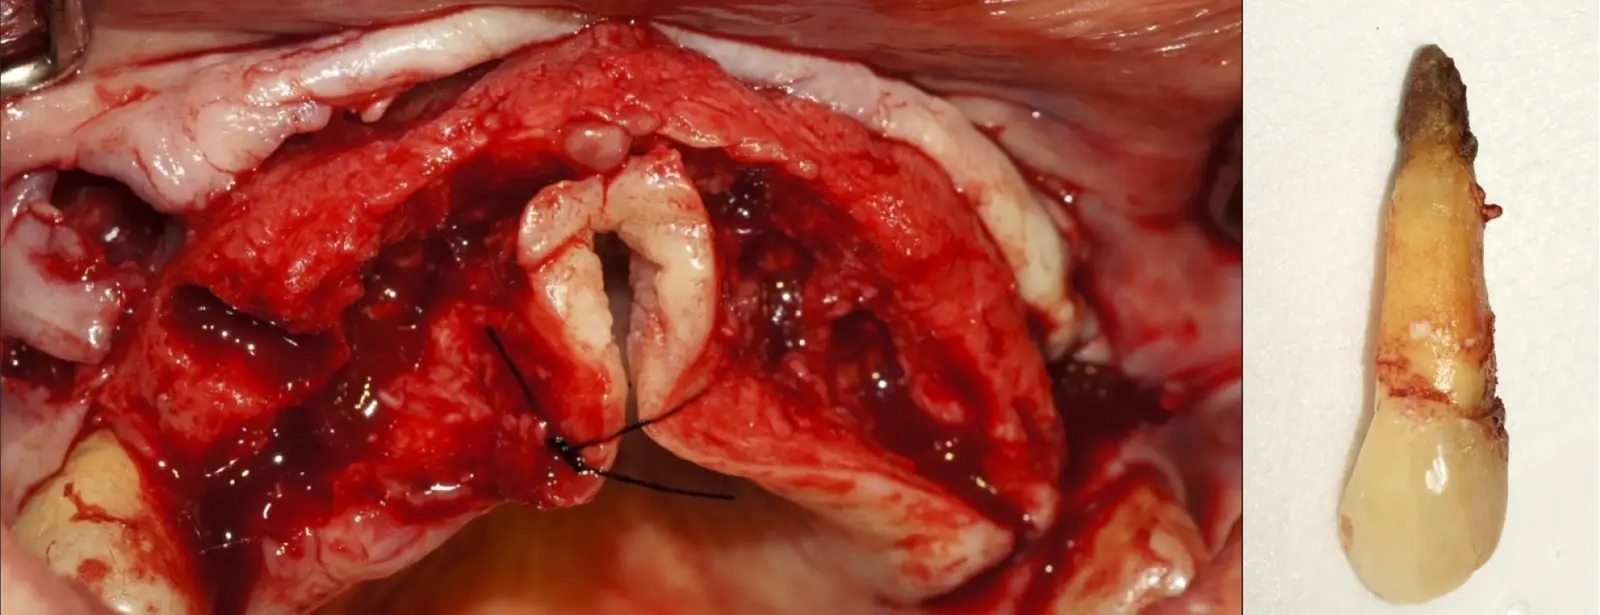

Una vez limpia la zona apical, se corrobora la integridad de la raíz y se evalúa el grado de extensión de la lesión. Si el defecto óseo es pequeño, se procede a realizar la preparación del conducto y obturación retrógrada de ser el caso. Si el defecto óseo es de gran tamaño e inaccesible a los insertos, se procede a realizar un corte de por lo menos 3 mm de ápice radicular conteniendo los posibles conductos aún infectados11 empleando habitualmente insertos de borde aserrado con/sin marcas de medición para un trabajo seguro7 (Figura 7).

Aunque algunos autores recomiendan evitar los ángulos en bisel para no exponer excesivamente túbulos dentinarios por riesgo de una posterior microfiltración18, en la cirugía apical piezoeléctrica recomendamos realizar un bisel externo para tener un mejor acceso al ápice. La configuración de los insertos de piezoeléctrico permiten realizar un corte lo más cercano a los 0°-10° de bisel11 con acceso adecuado a la zona de posterior obturación (Figura 8).